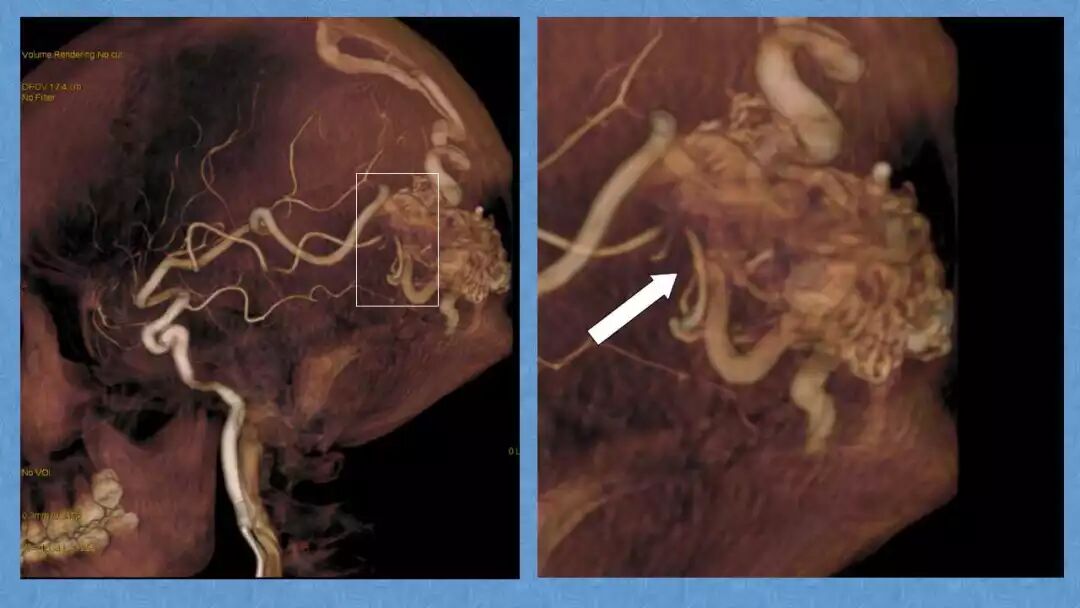

今天为大家分享的是《贝朗时间》第二十九期,湖北十堰市太和医院神经外科张力教授团队带来的:一个AVM患者的48小时纪实,欢迎阅读、分享!

张力教授:AVM切除术